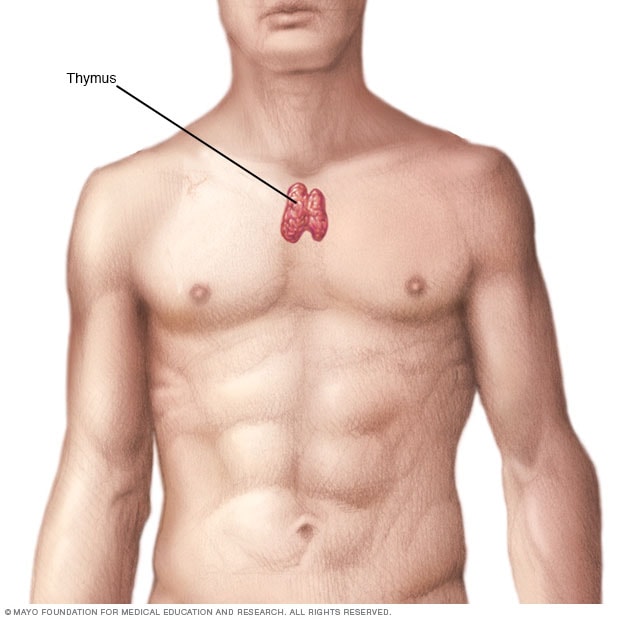

Фотографии вилочковой железы тимуса: структура и функции